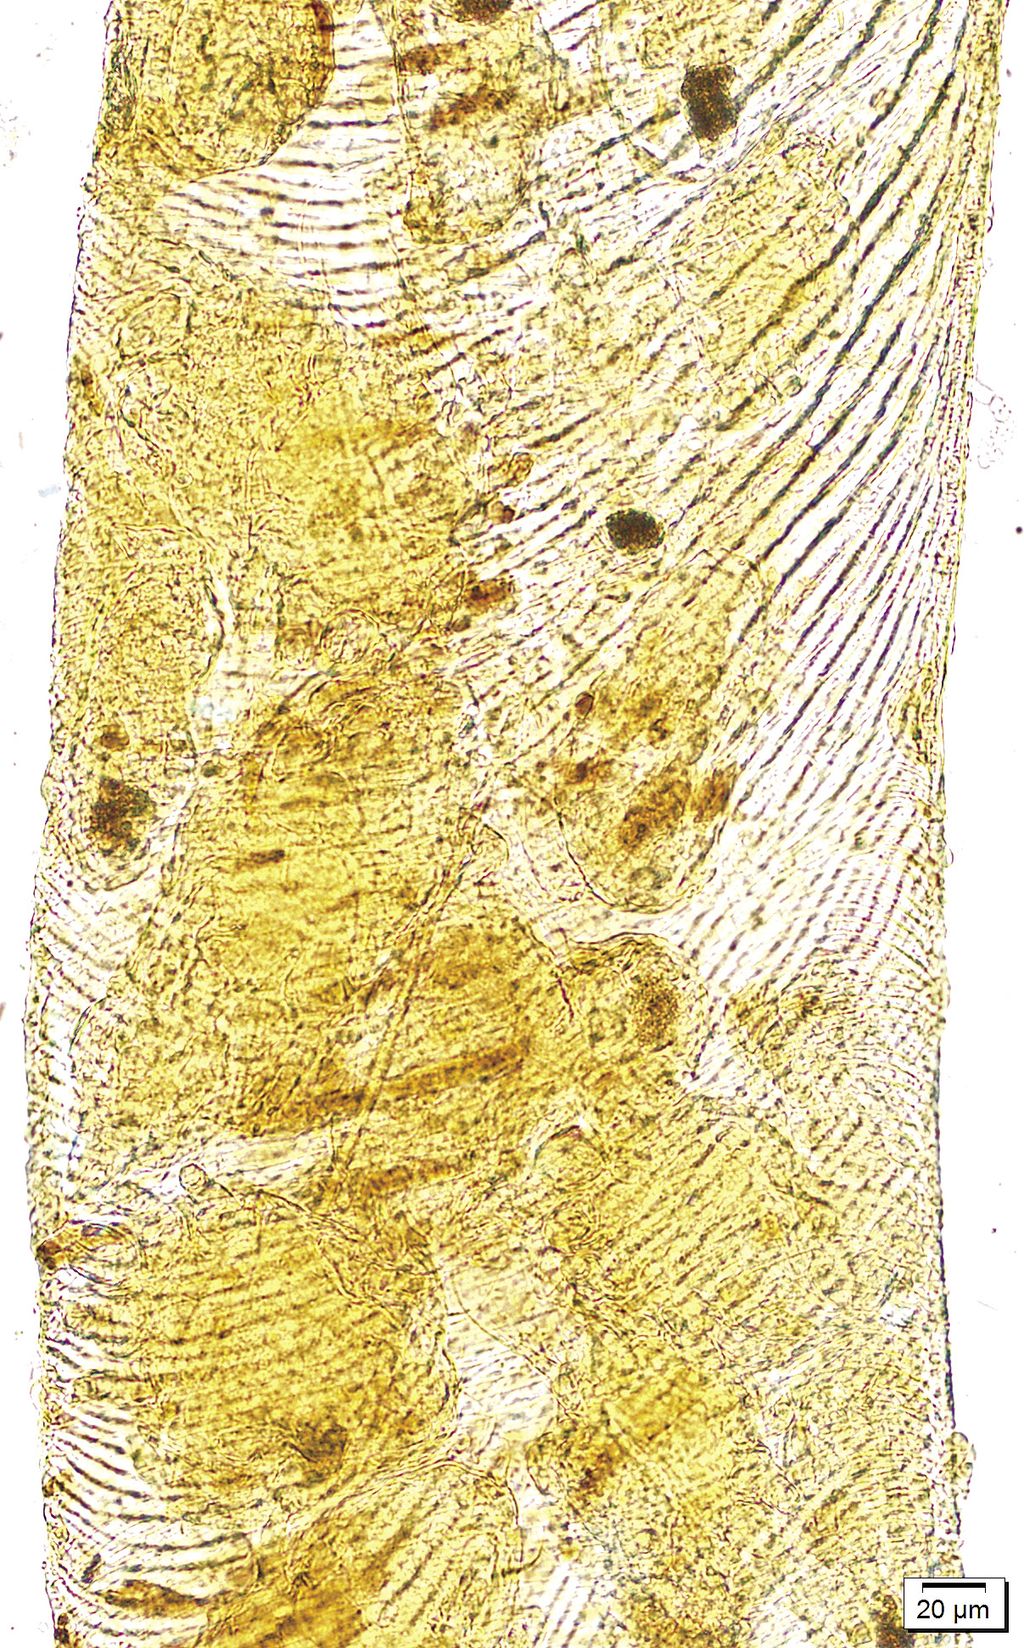

Foto 3. Sistemul traheal al albinelor. Fotograf Andrzej Bober

Acarapis woodi se hrănește cu hemolimfa de albine care curge în interiorul tuburilor traheale din orificiile care apar ca urmare a acțiunii aparatului său bucal, pentru înțepat și supt, special construit.

Impactul negativ al parazitului asupra corpului unei albine infectate este rezultatul mai multor factori, printre care trebuie menționată obturarea parțială sau chiar completă a tuburilor traheale, datorită prezenței parazitului în ele, deteriorarea pereților tuburilor traheale, care poate fi poarta de acces a infecțiilor virale sau, în final, epuizarea asociată cu pierderea hemolimfei.

Afectarea fluxului de aer în sistemul respirator al albinei reduce semnificativ posibilitatea schimbului de gaze, care este extrem de important pentru buna funcționare a țesuturilor, în cadrul unor structuri deosebit de importante pentru albine, cum ar fi mușchii aripilor sau sistemul nervos, ceea ce duce la tulburări în funcționarea acestora.